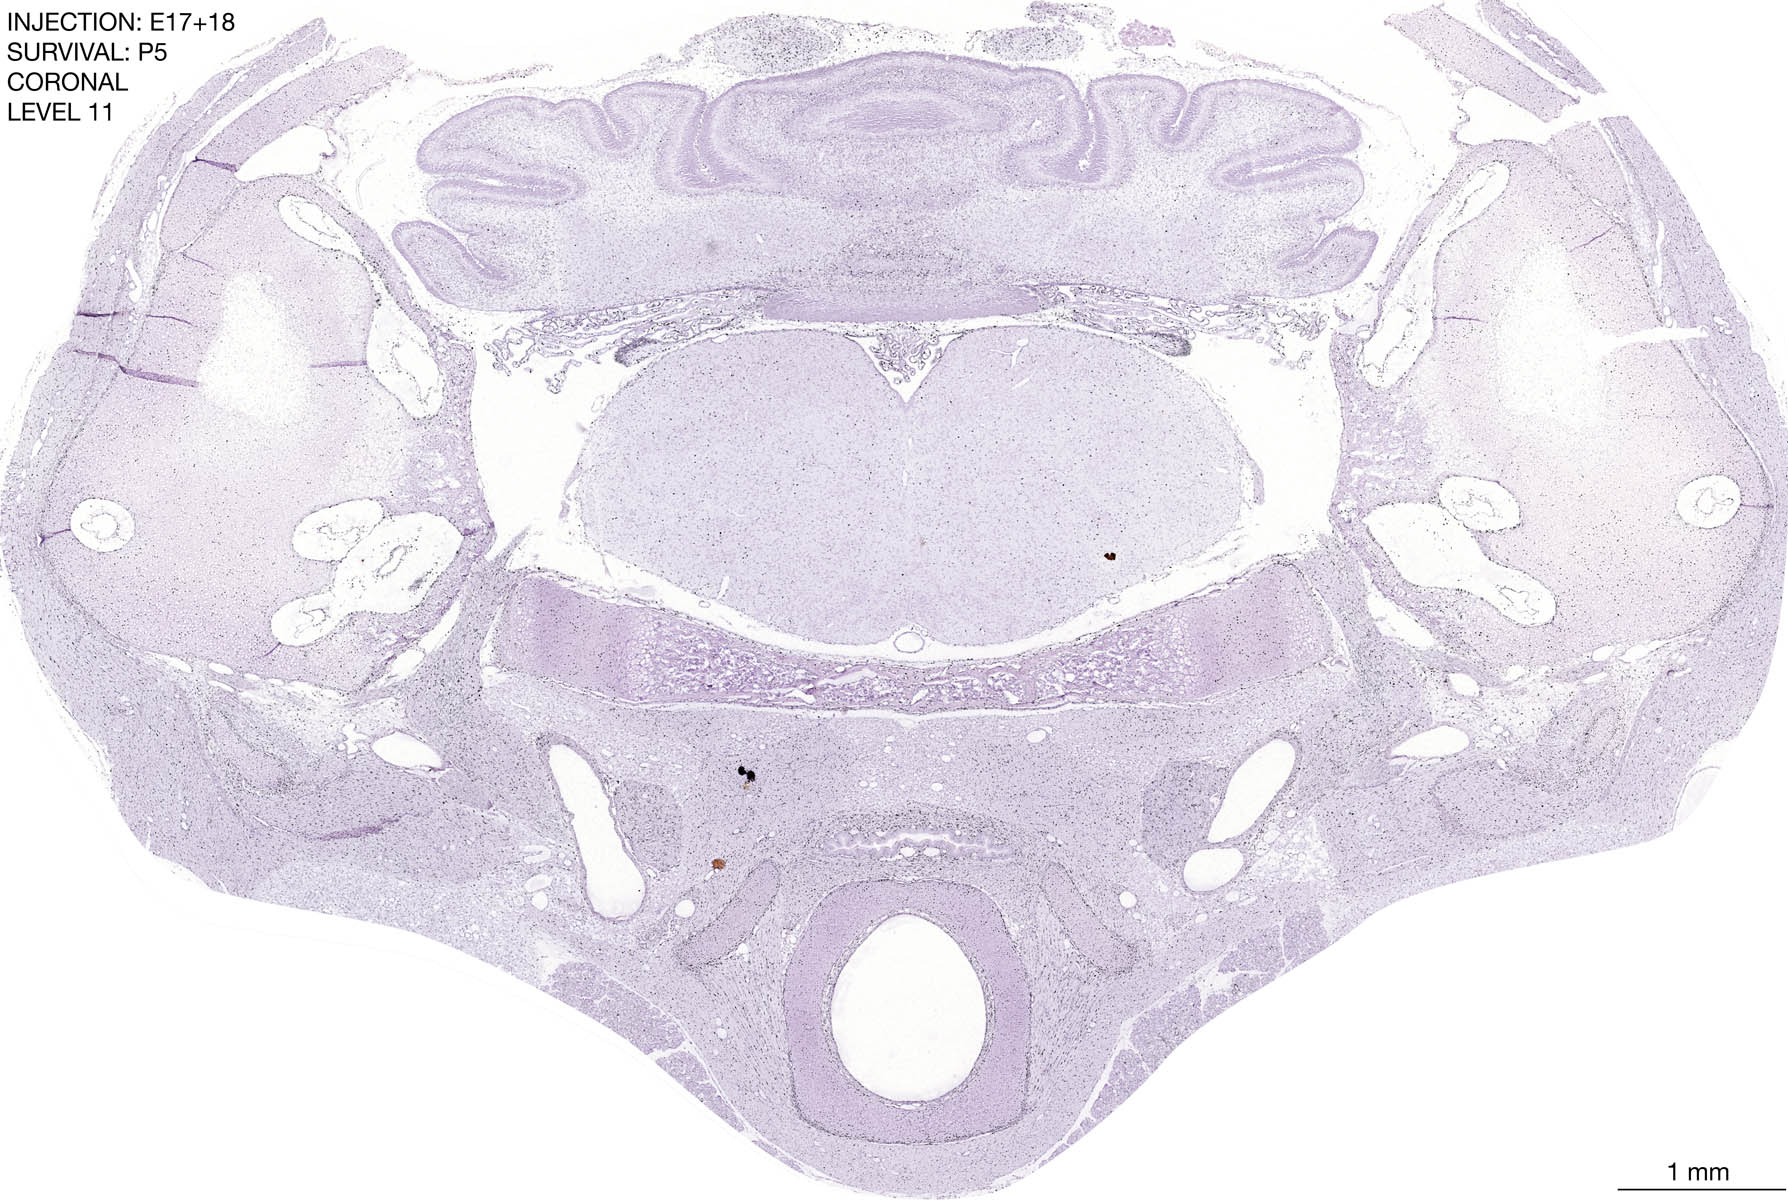

E17+18 P5 Survival The images below are from the brain of a rat that was exposed to tritiated thymidine on E17+18 and survived to P5. Download: Large | High Res Download: Large | High Res Download: Large | High Res Download: Large | High Res Download: Large | High Res Download: Large | High Res Download: Large | High Res Download: Large | High Res Download: Large | High Res Download: Large | High Res Download: Large | High Res Download: Large | High Res Download: Large | High Res Download: Large | High Res Download: Large | High Res Download: Large | High Res Download: Large | High Res Download: Large | High Res Download: Large | High Res Download: Large | High Res Download: Large | High Res Download: Large | High Res Download: Large | High Res Download: Large | High Res Download: Large | High Res Download: Large | High Res